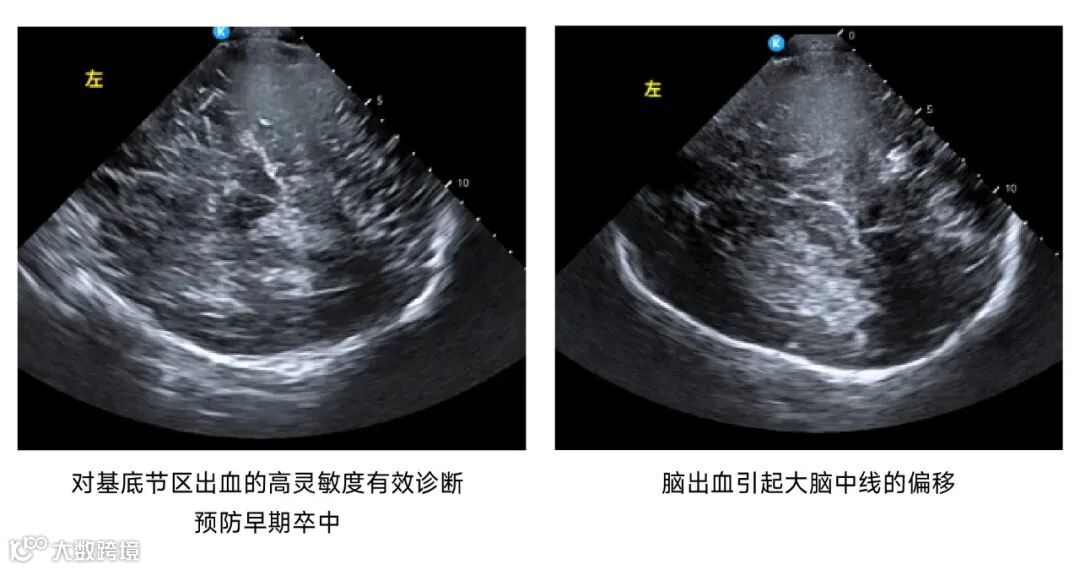

鲲为科技基于kOS带来的超分辨成像技术和超穿探头,

进一步拓展了颅脑超声的应用场景,

在神经内科、神经外科、神经重症监护监测、急诊重症监护、儿科及神经调控等领域带来革命性的创新诊断方案。